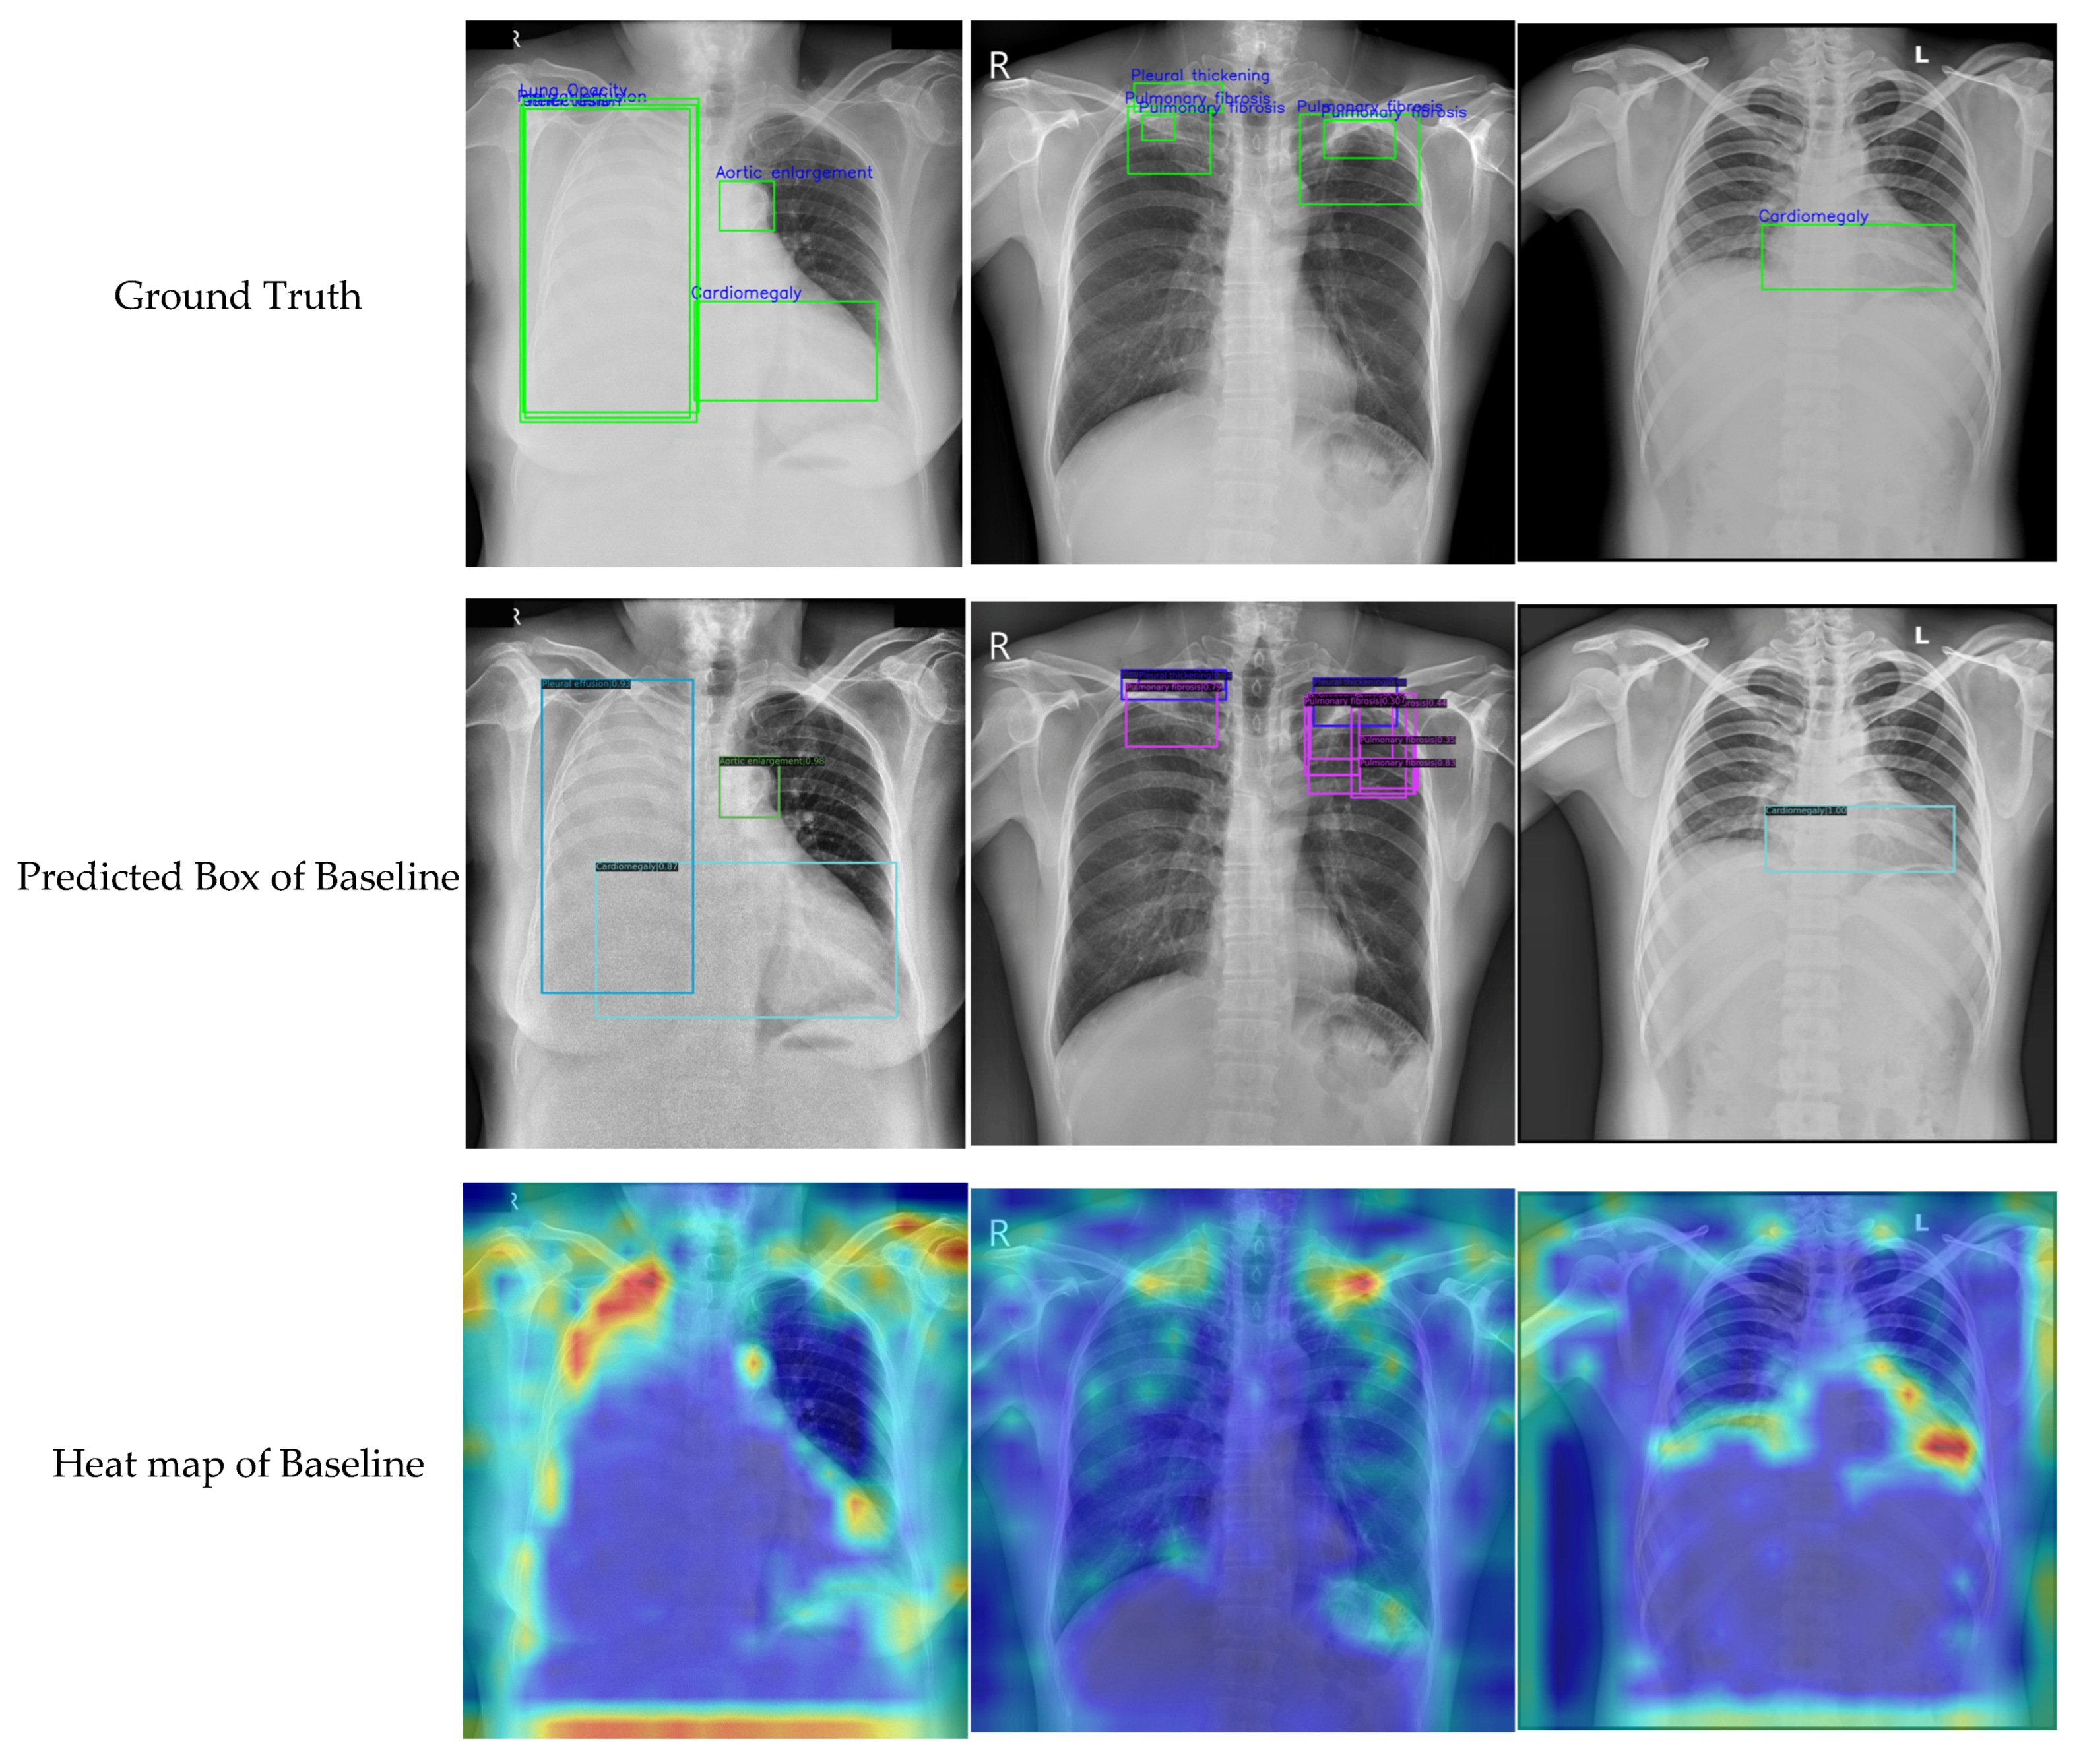

Because the chest X-ray abnormalities were independently labeled by three professional radiologists, many overlaps in annotation boxes were found in the VinDr-CXR dataset. Therefore, the weighted box fusion (WBF) technology [42] was used to reduce the overlap and redundancy of the annotation boxes. In Figure 5, the left image shows the original label and the right image shows the result obtained using WBF. It can be observed that the annotation box was significantly smaller and more concise after pre-processing. In addition, the original chest X-rays had a low contrast and brightness, which may have influenced the learning effect. For this reason, we performed image pre-processing for each sample through histogram equalization, and the results are shown in Figure 6.

Figure 5.

The pre-processing for label box: (a) original label in the VinDr-CXR dataset; (b) optimized annotation result obtained using WBF. The red box indicates the location of the chest abnormality.